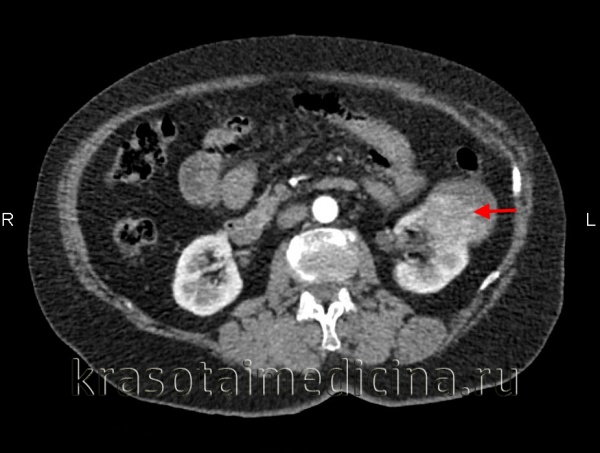

УЗИ почек является первым инструментальным обследованием при подозрении на почечно-клеточный рак. Характерными эхографическими признаками служат увеличение размеров почки, неровность контуров, изменение эхоструктуры, деформация почечных синусов и чашечно-лоханочных комплексов. УЗДГ сосудов почек позволяет определить характер васкуляризации опухоли и вовлеченность сосудов.

2. УЗИ при почечноклеточном раке:

• Серошкальное ультразвуковое исследование:

о Внешний вид варьирует: солидный, кистозный или смешанный

о Гиперэхогенный (48%), изоэхогенный (42%) или гипоэхогенный (10%)

о Небольшие опухоли обычно гиперэхогенные; имитируют ангиомиолипому (АМЛ)

о Крупные опухоли, как правило, гипоэхогенные, экзофитный рост с анэхогенными очагами некроза о Гипоэхогенный ободок, напоминающий «псевдокапсулу» о Кистозный вариант: однокамерный или многокамерный, уровень жидкость-взвесь (кровоизлияние и некроз), утолщенные неровные стенки или перегородки, узелки